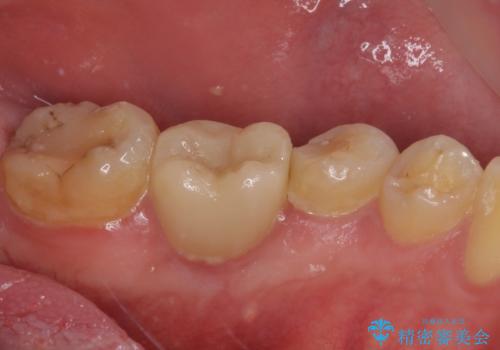

セラミッククラウンによる奥歯のむし歯治療

- 奥歯がしみて痛いとのことで来院された患者様です。

既に複数箇所の修復が行われていたため、オールセラミッククラウンにて補綴をすることとしました。

以前装着した修復物が不適であり、歯肉が腫れていましたが、仮歯を装着したことで腫れは解消されました。

歯の痛みだけでなく、歯肉の腫れも改善され、患者様には大変満足していただきました。